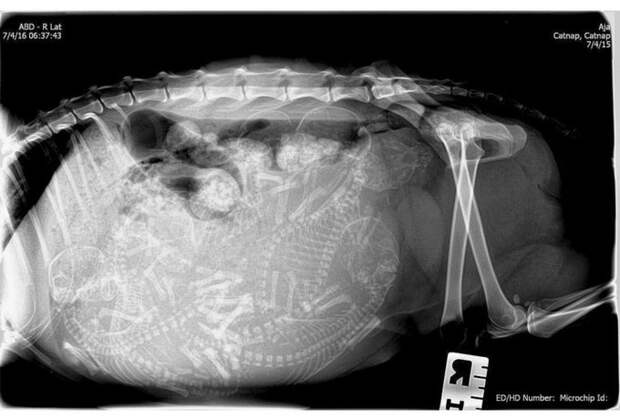

Беременная черепаха.